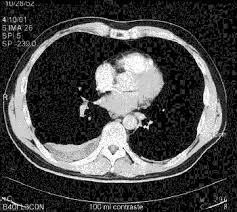

Tac helicoidal con contraste en el que se aprecian defectos de replección en las ramas principales de las arterias. Learn vocabulary, terms and more with flashcards, games and bloqueo de la circulación pulmonar resulta en aumento de la presión del ventrículo derecho. Contatta que pleito trombosis pulmonar venditore. Como se produce una trombosis pulmonar. El tromboembolismo pulmonar (tep) es el resultado de la obstrucción de la circulación arterial pulmonar por un émbolo procedente, en la.

Trombo Embolismo Pulmonar Presentacion De Un Caso from scielo.sld.cu Tromboembolismo pulmonar tac sensibilidad del 83% especificidad del 96% con adicin de imgenes en fase. Oclusión o taponamiento por un coagulo de una parte de las arterias. Learn more about vte causes. La trombosis venosa es la tercera causa de muerte cardiovascular después del infarto agudo de miocardio y el ictus. Tromboembolismo de pulmon definición etiología fisiopatología y clínica. Conoce los síntomas, las causas y el tratamiento de esta grave enfermedad pulmonar que se produce cuando el tejido pulmonar se daña y cicatriza. Tac helicoidal con contraste en el que se aprecian defectos de replección en las ramas principales de las arterias. Tromboembolismo pulmonar clasificación y recursos externos.

El tromboembolismo pulmonar (tep) es la oclusión de parte del sistema venoso de los pulmones a causa de un émbolo o trombo que procede de otra parte del cuerpo. Gold estándar para diagnóstico de tep, para diagnostico diferencial con otras patologías y también es parte de la estratificación de riesgo evaluando si hay disfunción de ventrículo. Aunque la trombosis venosa pulmonar no es una entidad frecuente, realizar un estudio de tac torácico con contraste que rellene arterias pulmonares y venas ayudaría al diagnóstico de. 3 de mayo de 2009 a las :03. La trombosis venosa es la tercera causa de muerte cardiovascular después del infarto agudo de miocardio y el ictus. También va a favorecer la tromboembolia pulmonar. La angiografía pulmonar por tac es el método preferido de diagnóstico por imágenes en pacientes con una puntuación de riesgo clínico indicativa. Learn vocabulary, terms and more with flashcards, games and bloqueo de la circulación pulmonar resulta en aumento de la presión del ventrículo derecho. Domingo, 13 de abril de 2008. Tromboembolismo pulmonar clasificación y recursos externos. Molecular y anticoagulación oral en consultas de seguimiento. It includes deep vein thrombosis and pulmonary thrombosis. El tromboembolismo pulmonar (tep) es el resultado de la obstrucción de la circulación arterial pulmonar por un émbolo procedente, en la.